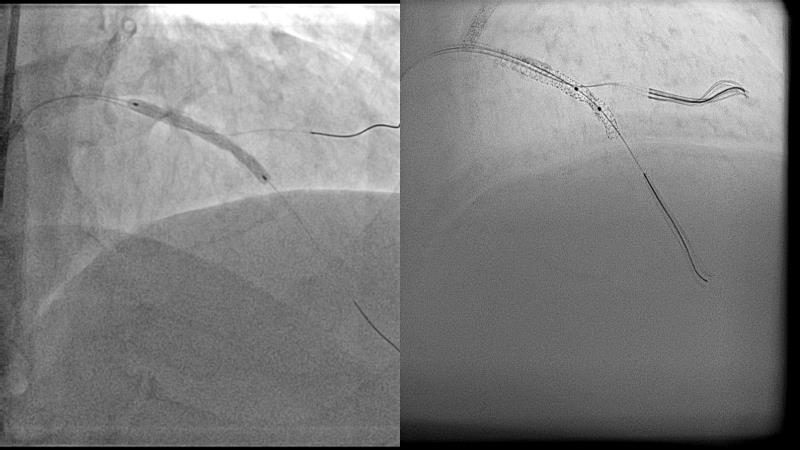

Cracking calcium: best practices to integrate intravascular lithotripsy into your calcium management algorithm

With this session, keep up to date on the evidence, trials and outcome data for intravascular lithotripsy in severely calcified lesions. Learn how to use this technique in real-world patients and understand its role in the treatment algorithm for severely calcified coronary lesions.